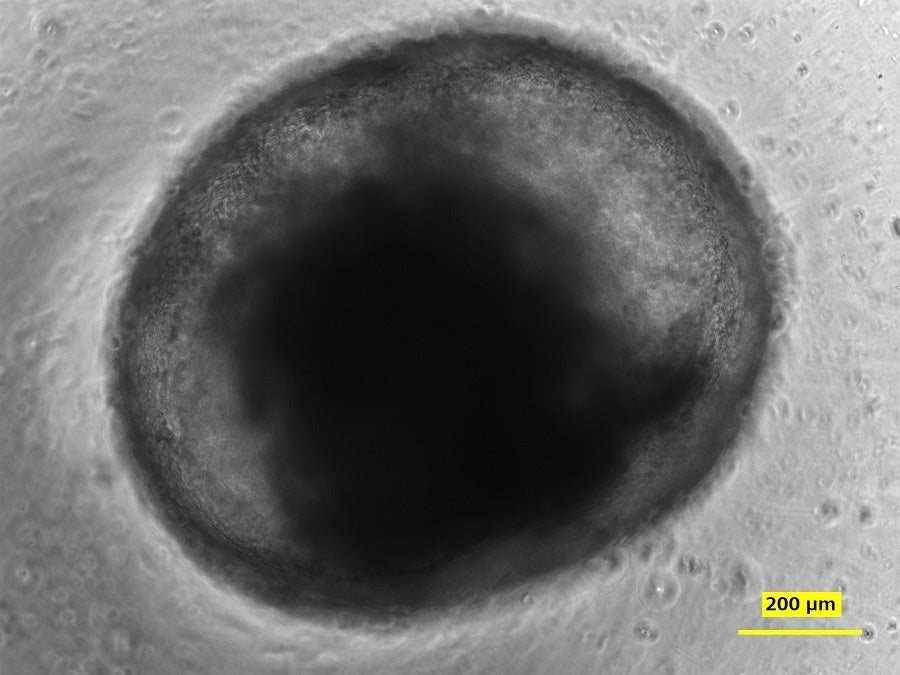

ミニ腸を用いた標識試薬(緑)の吸収反応の観察画像

ミニ腸は生体に類似した立体構造を持ち、形状を維持したまま、さまざまな機能性物質を作用させることができると知られてきました。本研究では、ミニ腸が実際に立体構造を保持したまま、蛍光標識した三大栄養素を吸収させ、糖質の吸収抑制効果がある成分をミニ腸に作用させたところ、糖質の吸収が抑えられることを確認しました。なお、ミニ腸の大きさの測定には、DNPが開発したAIをベースにした測定ソフト*を使用しています。